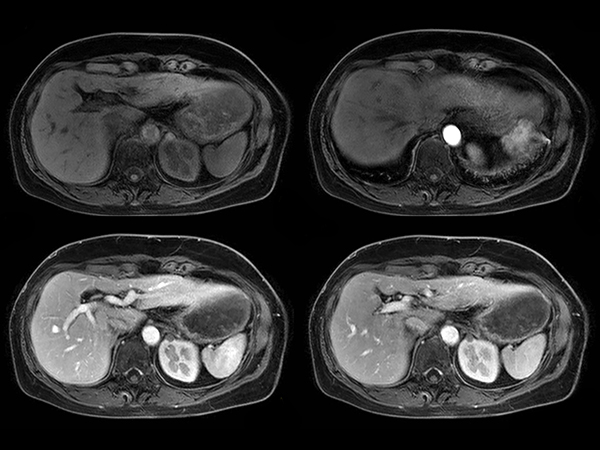

Axial dynamic mDIXON - Water dS SENSE = 7.5